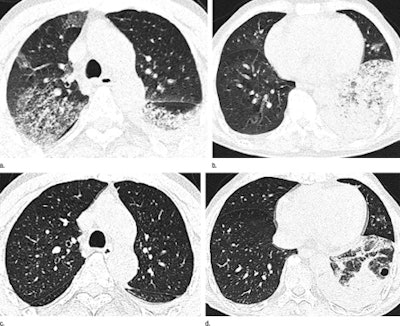

Axial thin-section CT images in 65-year-old man with H7N9 influenza. Top row, initial images obtained at admission show extensive GGOs and consolidation. Bottom row, images at seven-day follow-up show complete resorption of the lesion in the right upper lobe and partial resorption in the left lower lobe with a round cystic change. Images republished with permission of RSNA from Radiology July 2, 2013.Additional findings included consolidations, bronchograms, and interlobular septal thickening (each in 11 patients). Less common were centrilobular nodules (seven patients), cystic changes (four patients), and bronchial dilatation and subpleural linear opacities (each in three patients), Wang and colleagues wrote.

At CT, all patients had lung lesions affecting three or more lobes with a bilateral distribution, but patients were usually affected more on one side than the other, the group reported. The right lung was more affected in seven patients and the left lung in three, with roughly equal distribution in two patients. Extensive GGOs were the most prominent feature, seen in all 12 patients, though some individual lobules were unaffected.

At radiography, the investigators found increased heterogeneous opacity in the lung fields with either a bilateral or unilateral distribution, most commonly affecting the right lower lung (n = 11). Air bronchograms were always seen in the area of consolidation, and the margins were clear when adjacent to the interlobar fissure. Abnormalities could generally be seen within one week after symptom onset; regression in three patients and progression in four corresponded to radiographic results, the authors wrote.

Rapidly progressing GGOs and consolidations with air bronchograms and interlobular septal thickening, all with a right lower lobe predominance, are the main imaging findings seen with H7N9 pneumonia, the authors concluded. The severity of these findings corresponded to disease severity at presentation.